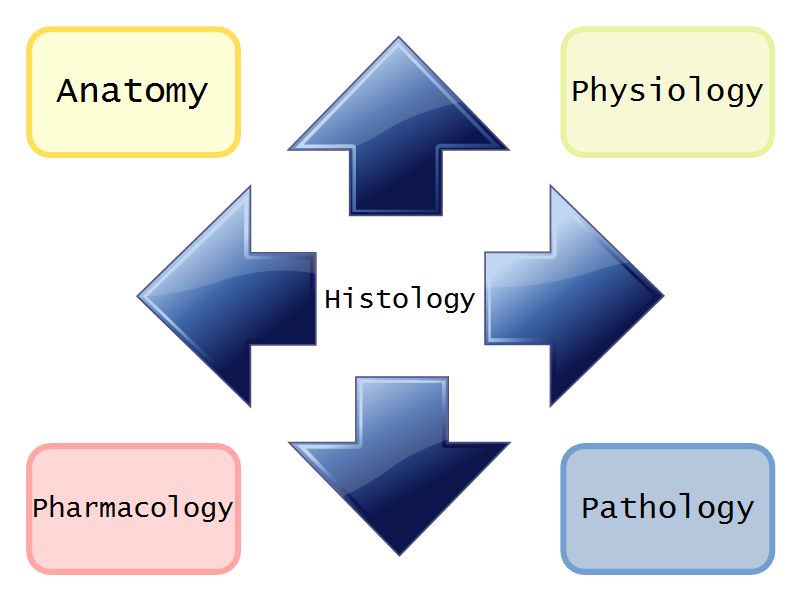

Where does Histology fit?

Why histology?

- Knowledge

- Because all knowledge is worthwhile

- The more you know, the more you are able to know

- Know the normal to identify the abnormal

- Pathology

- Functions of many organs

- Lung, Kidney, Liver

- Informed by cellular organisation

- Physiology

- Structure of body informed by cellular organisation

- Anatomy

- Inflammation, Repair & Treatment dependent on cellular organisation

- Pharmacology